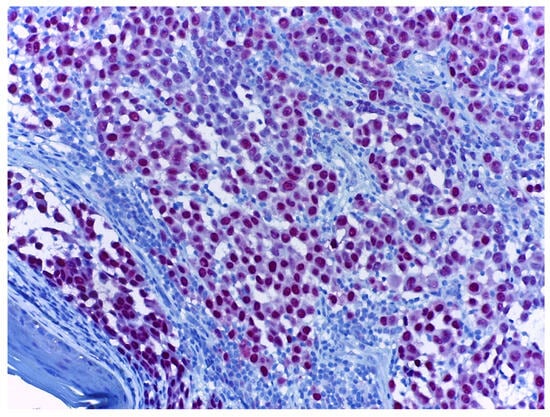

3.7. PRAME

- Parra, O.; Linos, K.; Li, Z.; Yan, S. PRAME Expression in Melanocytic Lesions of the Nail. J. Cutan. Pathol. 2022, 49, 610–617. [Google Scholar] [CrossRef]

- Lezcano, C.; Jungbluth, A.A.; Busam, K.J. Immunohistochemistry for PRAME in Dermatopathology. Am. J. Dermatopathol. 2023, 45, 733–747. [Google Scholar] [CrossRef] [PubMed]

- Lezcano, C.; Jungbluth, A.A.; Nehal, K.S.; Hollmann, T.J.; Busam, K.J. PRAME Expression in Melanocytic Tumors. Am. J. Surg. Pathol. 2018, 42, 1456–1465. [Google Scholar] [CrossRef]

- Wakefield, C.; O’Keefe, L.; Heffron, C.C.B.B. Refining the Application of PRAME-a Useful Marker in High CSD and Acral Melanoma Subtypes. Virchows Arch. Int. J. Pathol. 2023, 483, 847–854. [Google Scholar] [CrossRef]

- Alomari, A.K.; Tharp, A.W.; Umphress, B.; Kowal, R.P. The Utility of PRAME Immunohistochemistry in the Evaluation of Challenging Melanocytic Tumors. J. Cutan. Pathol. 2021, 48, 1115–1123. [Google Scholar] [CrossRef]

| PRAME | Suitable for differential diagnosis between benign and malignant melanocytic lesions. |